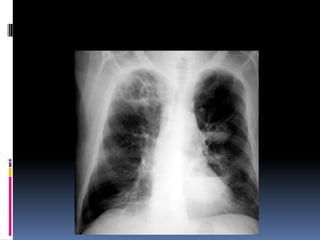

Heart

   Size

   Shape

   Silhouette-margins should be sharp

   Diameter (>1/2 thoracic diameter is

enlarged heart)

 AP views make heart appear larger than it

actually is.

Costo-phrenic / cardiophrenic angles

Margins should

be sharp

Heart  Size  Shape  Silhouette-margins should be sharp  Diameter (>1/2 thoracic diameter is enlarged heart)  AP views make heart appear larger than it actually is.

Costo-phrenic / cardiophrenicangles Margins should be sharp